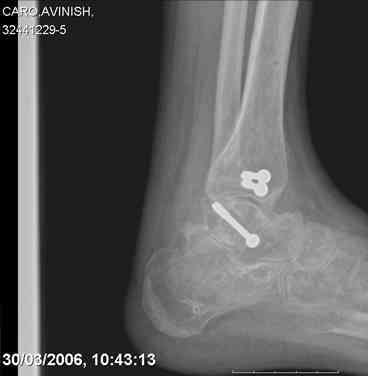

ya by popytalsya sobrat talus anatomichno,seichas pozdno operirovat iz za oteka,po etomy distrakziya apparatom budet optmalna.Posyalu vam podobyai moi sluchai.

14 years old girl

Fall from height ( 3rd floor)